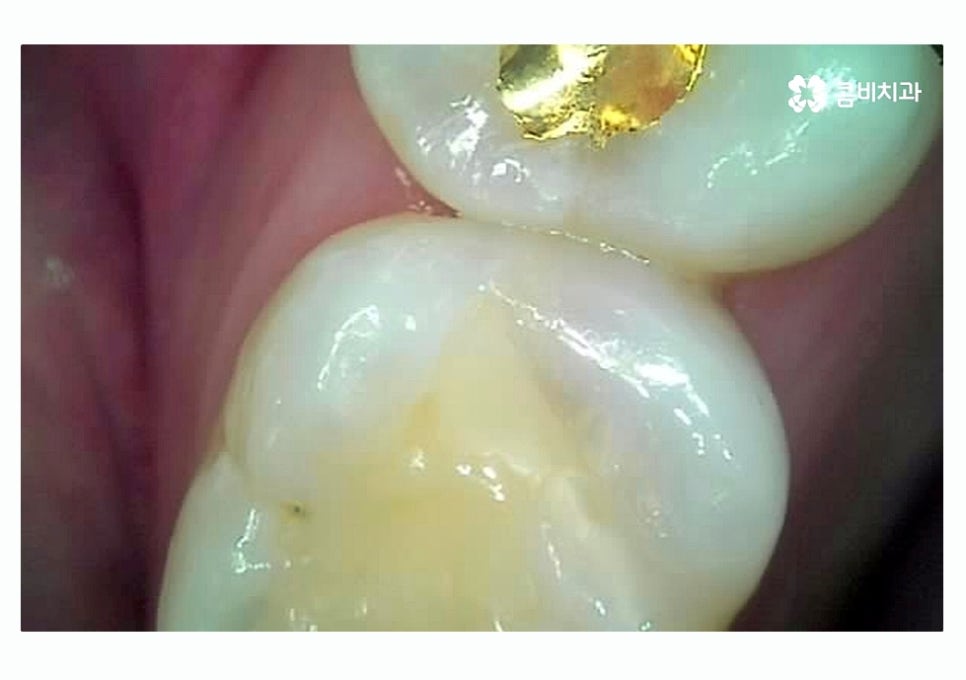

성인 이후에 자주 발생되는 충치 유형 중에 하나는

치아의 인접면 충치라고 할 수 있는데요.

대표적으로 어금니와 사랑니 사이에 발생하기 쉽고

나이가 들면서 잇몸이 내려가고 그 사이 틈이 생길 수 있는데요.

식사 후 음식물이 치아 사이에 낀 채로 방치될 경우에는

인접면 충치가 발생하기 쉽기 때문에 칫솔질 후에

치실 사용을 습관화하는 것이 중요할 수 있어요.